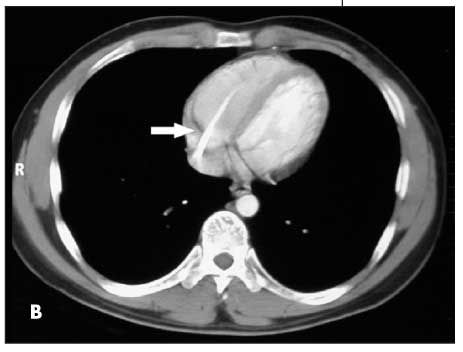

Figures B, C, and D are from a 17-year-old boy with Ewing sarcoma of the left hemipelvis. Fluoroscopy was used to confirm catheter placement, and blood return and ease of flushing the catheter were verified. During a routine clinic visit 18 months later, the patient complained of a cough and “feeling funny.” A chest radiograph was read as normal. A CT scan of the chest, obtained for routine evaluation of possible metastasis, was also interpreted as normal. However, embedded in the radiologist’s report was the comment, “A unipolar transvenous pacemaker has been placed with its tip in the right ventricular apex.” What the radiologist noticed was actually a fractured piece of CVC tubing (Figure B, arrow). Careful inspection of the patient’s earlier “normal” chest radiograph showed the fractured piece of tubing within the right atrium and ventricle (Figure C, arrow). A second chest radiograph showed the tubing fragment lodged in the right pulmonary artery extending into the right lung (Figure D, arrows). No POS was seen in a review of the patient’s radiographic records.

The second case highlights the necessity of careful inspection of all radiographic images ordered and their respective reports. The “funny feeling” the patient had been experiencing may have been related to cardiac arrhythmias caused by stimulation of the right ventricle by the detached tubing fragment.